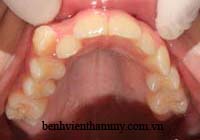

Trường hợp bệnh nhân người lớn - Răng mọc chen chúc niềng răng không nhổ răng:

(Hình ảnh trước điều trị)